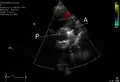

PDA

An echocardiogram of a stented persisting ductus arteriosus: One can see the aortic arch and the stent leaving. The pulmonary artery is not seen.

An echocardiogram of a coiled PDA: One can see the aortic arch, the pulmonary artery, and the coil between them.